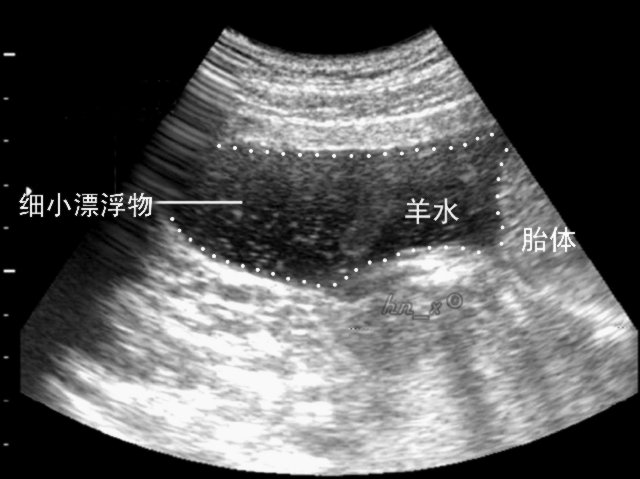

正常羊水的量随妊娠时期的不同而变化,一般来说,在妊娠4个月左右时,羊水量约200毫升,7个月左右时,羊水量则为1000毫升左右,到妊娠晚期,羊水量逐渐减少,到妊娠37周,羊水量可减少至800毫升。当妊娠足月时,羊水量小于300毫升,则称为羊水过少。

不过羊水过少平时没有多大的影响,所以大部分妈妈都不知道,这个只有在孕检的时候才知道,所以妈妈们一定要按时去孕检,这样就能知道羊水的多少了。如果发现羊水过少的情况,要听医生的建议,尽量让羊水保持在正常值范围内。